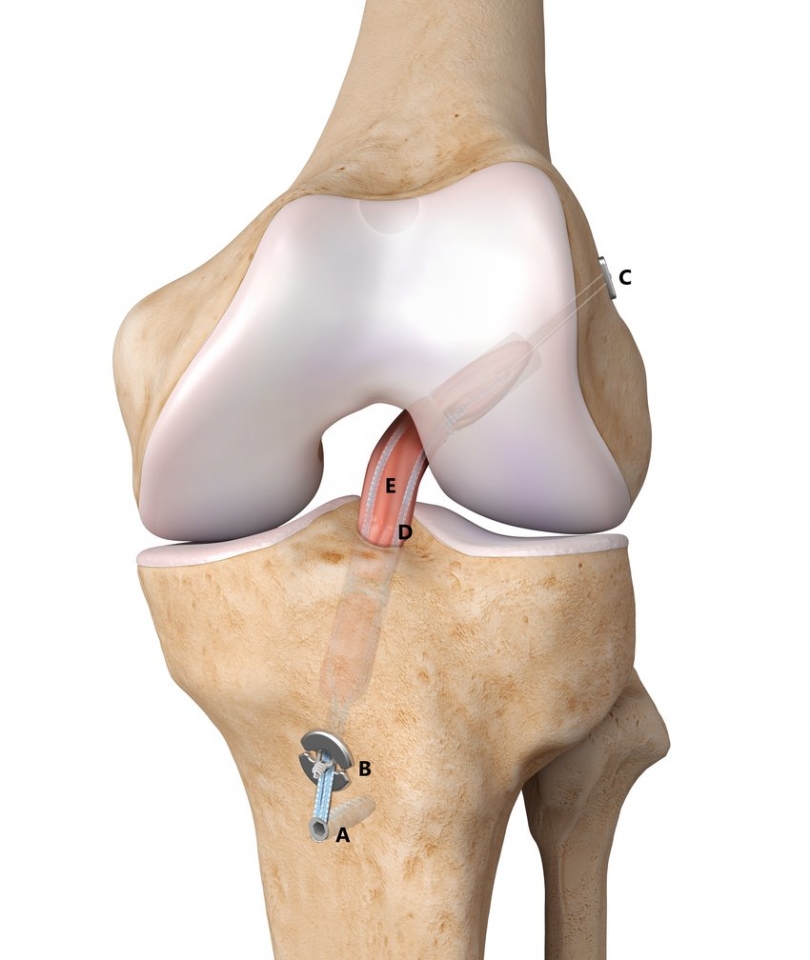

• Χειρουργικής Γόνατος, με έμφαση στην αρθροσκόπηση και ολική αρθροπλαστική

Συμμετείχε σε ετήσια βάση, σε διεθνή ιατρικά συνέδρια όπως επίσης και σε πτωματικά σεμινάρια για την εκμάθηση νέων χειρουργικών τεχνικών. Εξειδικεύτηκε στη διάγνωση και αντιμετώπιση παθήσεων και κακώσεων με ιδιαίτερη έμφαση στη αρθροσκοπική τεχνική και την αρθροπλαστική. Σημαντικό μέρος της πρακτικής του αποτέλεσε και το ορθοπαιδικό τραύμα όπως τα κατάγματα και οι αθλητικές κακώσεις καθώς εργάστηκε ως επιμελητής ειδικός Χειρουργός σε Τριτοβάθμια Νοσοκομεία και Μείζονα Κέντρα αναφοράς Τραύματος ενεργό μέλος πολυδύναμων ιατρικών ομάδων.